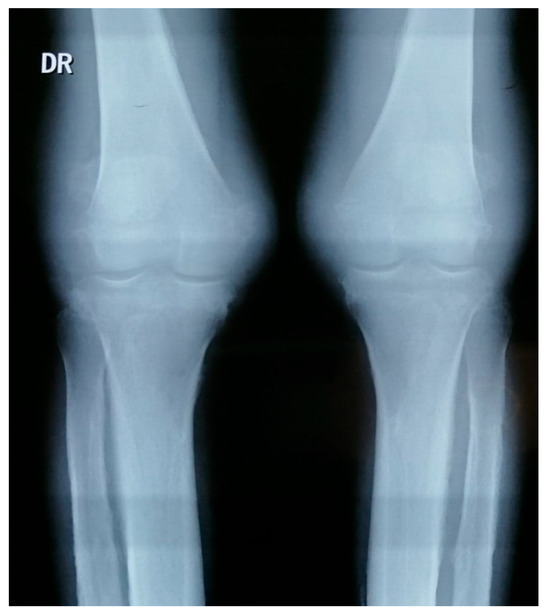

From Juvenile Idiopathic Arthritis to Pachydermoperiostosis: A Journey to an Unexpected Rare Diagnosis

Pachydermoperiostosis, also known as primary hypertrophic osteoarthropathy or Touraine–Solente–Golé syndrome, is a rare genetic disorder that represents a small fraction of hypertrophic osteoarthropathy cases. It typically begins during adolescence, affects males more frequently and follows either an autosomal dominant or recessive inheritance pattern. [...] Read more.

Pachydermoperiostosis, also known as primary hypertrophic osteoarthropathy or Touraine–Solente–Golé syndrome, is a rare genetic disorder that represents a small fraction of hypertrophic osteoarthropathy cases. It typically begins during adolescence, affects males more frequently and follows either an autosomal dominant or recessive inheritance pattern. The disease is characterized by the triad of pachydermia, periostosis and digital clubbing, often accompanied by hyperhidrosis, seborrhea, cutis verticis gyrata and joint effusions. Although articular involvement is usually non-erosive, the disorder may mimic inflammatory arthritis and lead to diagnostic delays. Recognition of the major and minor diagnostic criteria is crucial to distinguish PDP from secondary forms related to pulmonary, cardiac or neoplastic disease. Full article

(This article belongs to the Section Orthopedics)